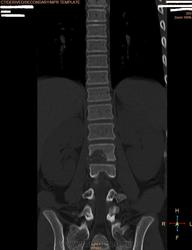

Здравствуйте коллеги.Прошу ваши помощи больной 1998 г.р. беспокоять боль поясничной области справа.Болеет в теч месяца, связывает с резким движением.Лечились по поводу почки без эфекта. Анализ не здали.Травму исключает. МРТ от 21 .10.2013 г. МР признаки участка патологич. измен. сигнальных характеристок с перифокальным трабекулярным отеком в теле и правой дужке позвон L2.Паравертабр. мягкотканный компонент в правой корешковой воронки на уровне L2-3.Этиология?Не исключается наличие осложненной переломы гемангиомы тела L2.Дифференцировать специфическим спондилитом .Анатомически суженный спинно- мозговой канал. Со слов матери костные фтизиатры исключили свое.Ваше мнение.

Образование позвонка, дифряд - ГКО, остеобластома, агрессивная гемангиома, солидный вариант АКК.